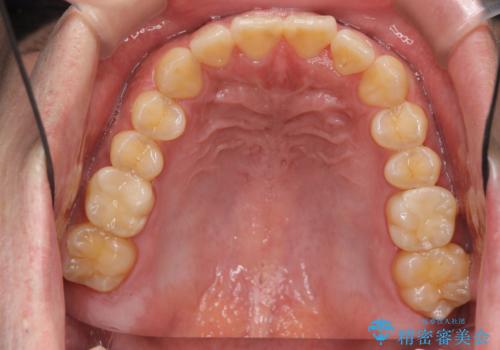

前歯のねじれを 1年かけずに矯正 インビザライン

- 前歯のねじれを主訴に来院。

インビザラインで治療しました。

前歯のねじれをセラミックで治そうとすると、抜髄といって、神経の治療が必要になる上、歯の幅も制限が出て理想的にはなりません。

保定の必要がありますが、天然歯を並べる矯正治療では、治療後の心配事が非常に少なく、保存的な処置となります。